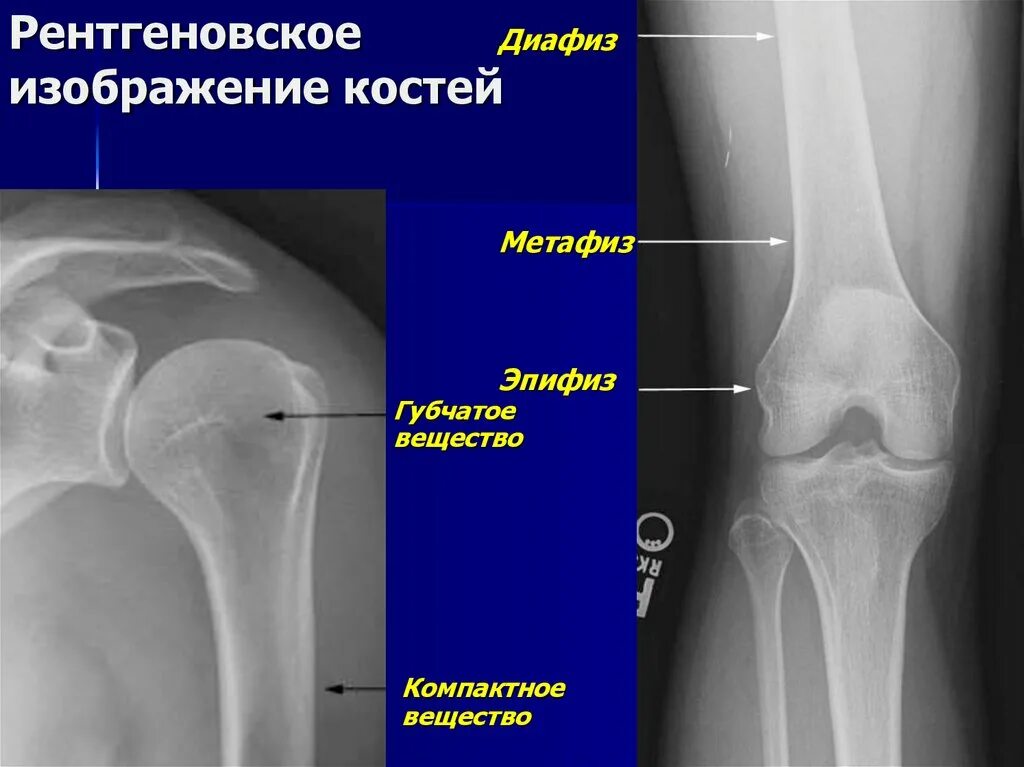

Снимок костей как называется